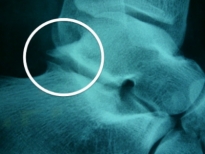

Que montre la radiographie

Elle met en évidence un pincement articulaire avec souvent une construction osseuse (ostéophyte) en arrière de l'astragale (au niveau de la zone du carrefour postérieur).

Cependant les radiographies peuvent parfois être proches de la normale.